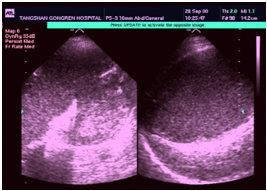

2.B型超聲檢查B型超聲檢查可顯示胰腺膿腫的有無、大小、數目和位置,但對嚴重急性胰腺炎有一定的限制。